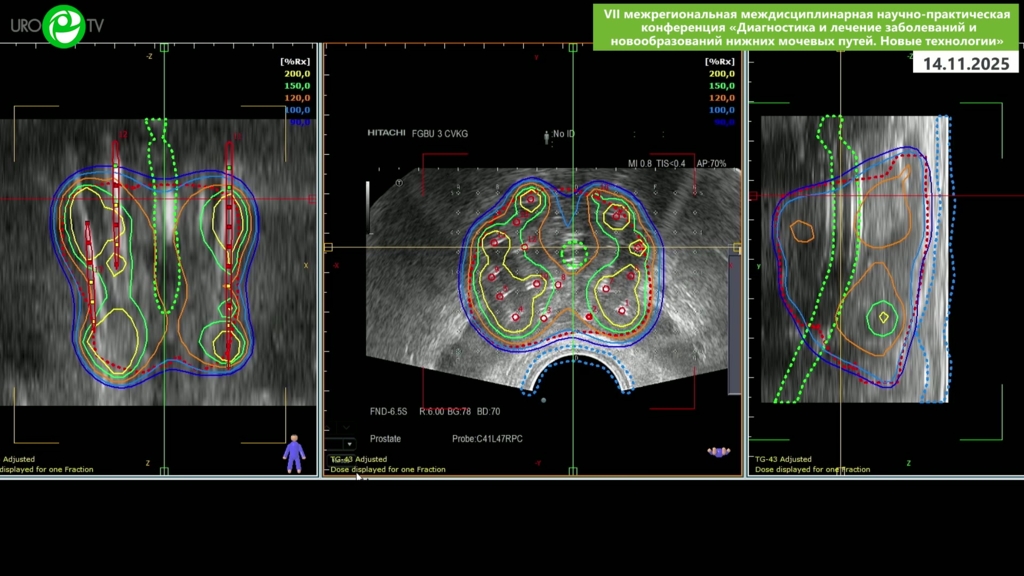

Цыбульский А.Д., Пчелинцев А.С. - Высокодозная брахитерапия локализованного рака простаты микроисточником Кобальт-60